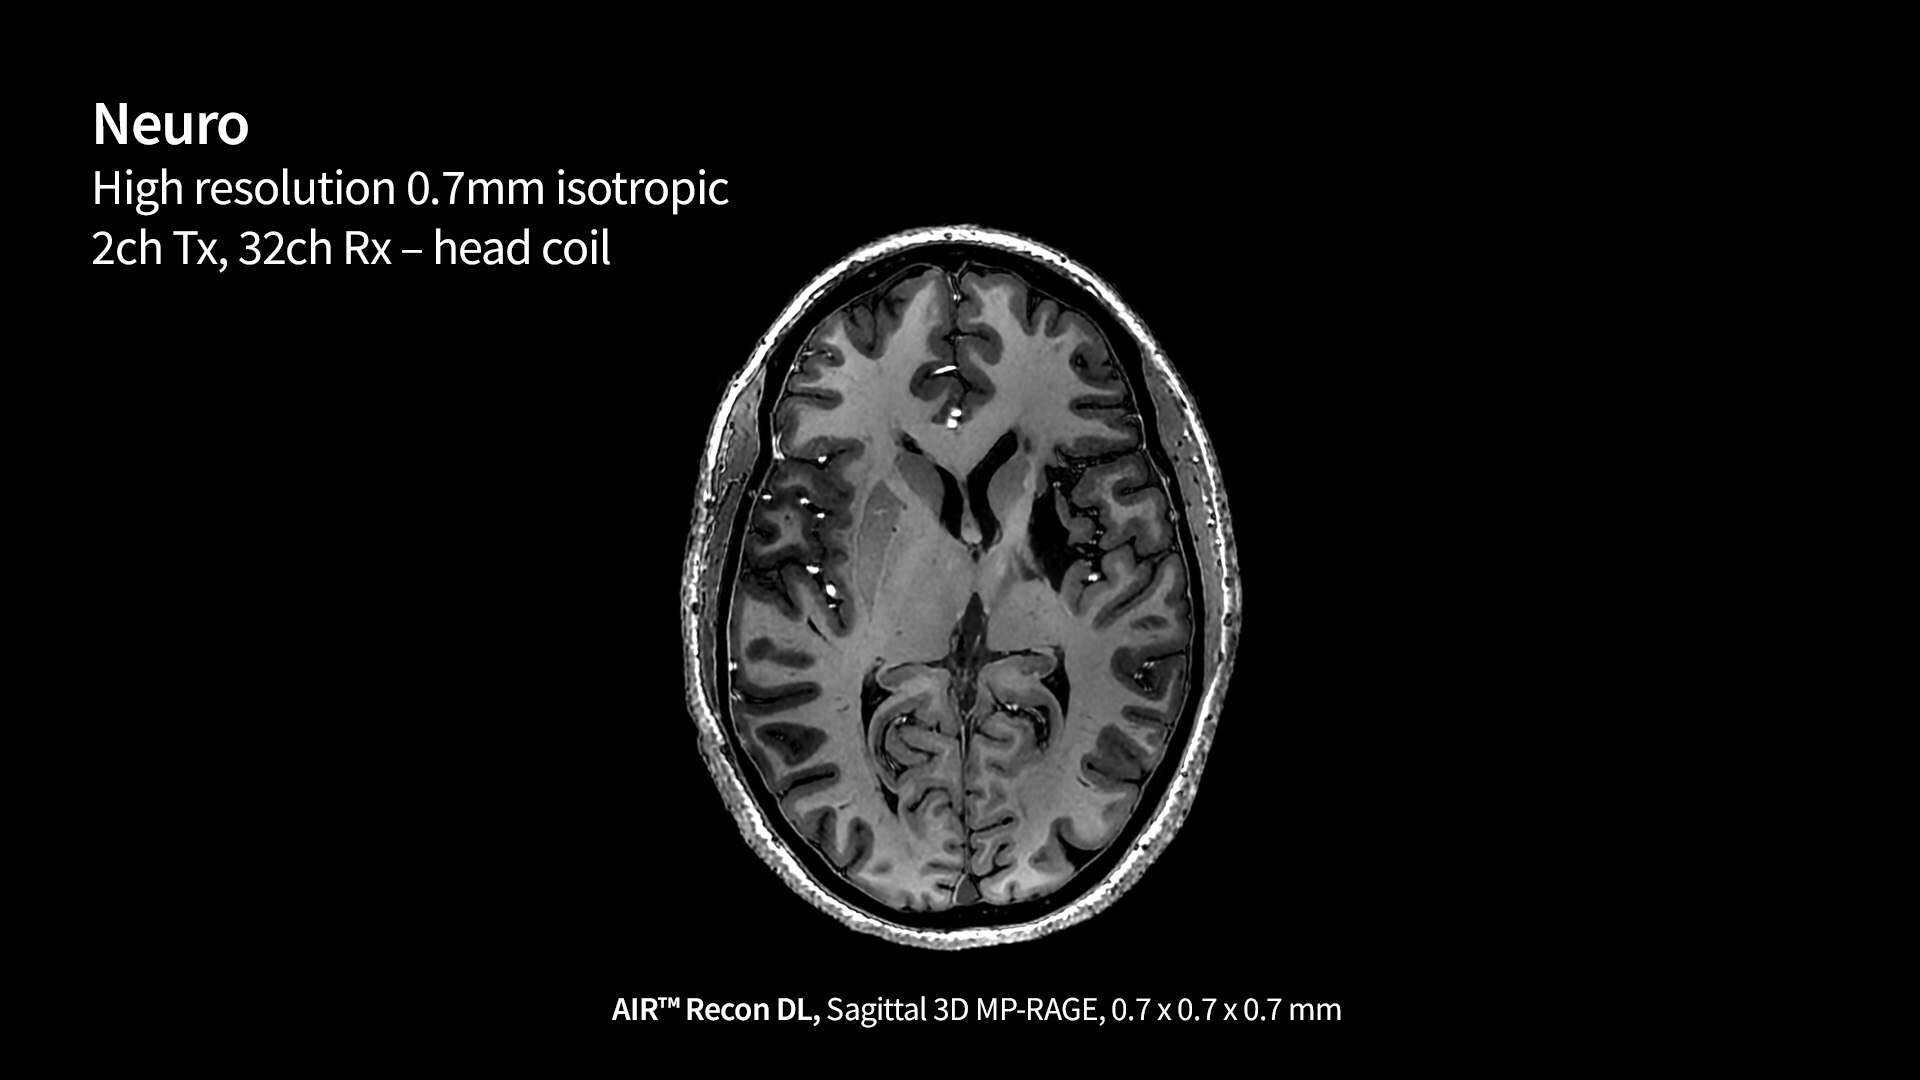

Construido sobre el éxito revolucionario de AIR™ Recon DL, nuestra primera innovación pionera en la reconstrucción de aprendizaje profundo, Sonic DL™ sigue con audacia sus pasos, avanzando en nuestra misión de revolucionar la RM. El aprendizaje profundo, cuando se aplica a la reducción del tiempo de exploración, convierte los minutos en segundos, lo que ofrece la rapidez de una TC y la calidad de una RM. Es mucho más rápido de lo que permiten las técnicas de aceleración convencionales actuales, lo que ayuda a los radiólogos a realizar diagnósticos precisos desde el principio.